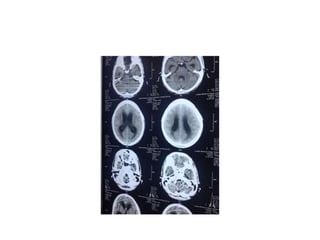

CT- HEAD

• Neuroimaging:

- CT & MRI are helpful in detection.

- CT can present the extent of basilar arachnoiditis,

cerebral edema and infarction, and the presence and

course of hydrocephalus.

• Hydrocephalus combined with marked basilar

enhancement is indicative of advanced meningitic disease

and carries a poor prognosis.

• Marked basilar enhancement correlates well with vasculitis

and, therefore, with a risk for basal ganglia infarction.